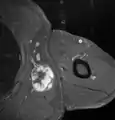

Medical ultrasonography and magnetic resonance imaging (MRI) of liposarcomas are helpful and often essential in determining their extent, surgical accessibility, and relationship to any observed organ dysfunctions. Since ultrasonography is usually unable to distinguish a liposarcoma from a benign lipoma, MRI is the initial imaging of choice to provide evidence relative to making this distinction.[67]

In myxoid liposarcoma, it shows low signal intensity mass with high signal intensity foci on T1-weighted MRI images. The mass shows high signal intensity on T2-weighted images. This is because it contains predominantly mucoid substance (accounts for low signal intensity on T1) and small amount of mature fat (accounts for high signal intensity on T1).[68] The mass is well-defined, lobulated, multiloculated, or oval in shape without any infiltration into surrounding structures.[68]

Fig. 7 MRI of myxoid liposarcoma of high grade, in the left axillary region of 40-year-old man, highlighted by its white color, in this horizontal section of the tumor. Fig. 7 MRI of myxoid liposarcoma of high grade, in the left axillary region of 40-year-old man, highlighted by its white color, in this horizontal section of the tumor.